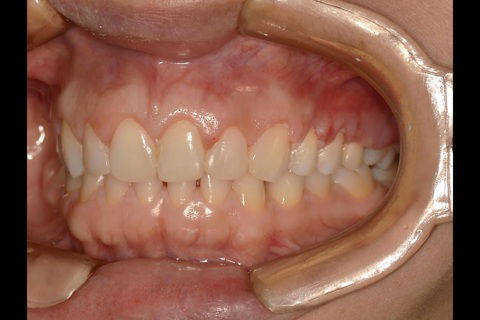

Fotos do caso